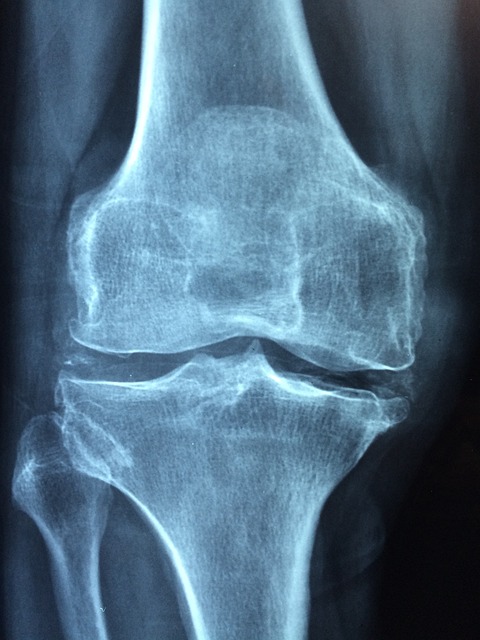

골다공증은 뼈 질량의 손실과 뼈조직의 퇴화를 특징으로 하는 의학적 상태로, 약해지고 깨지기 쉬운 뼈로 이어집니다. 골절이 발생할 때까지 눈에 띄는 증상 없이 진행되기 때문에 흔히 '조용한 질병'으로 불린다. "골다공증"이라는 단어는 말 그대로 "다공성 뼈"를 의미합니다. 일반적으로 뼈는 조밀한 외층과 강한 내층으로 구성됩니다. 골다공증에서는 이 내부 구조가 얇고 약해져서 골밀도가 감소하고 골절에 대한 취약성이 증가합니다. 골다공증의 영향을 받는 일반적인 부위에는 척추, 엉덩이, 손목 및 갈비뼈가 포함됩니다. 연령, 성별, 호르몬 변화(특히 여성의 폐경기), 낮은 칼슘 및 비타민 D 섭취, 좌식 생활 방식, 흡연, 과도한 알코올 섭취, 가족력, 특정 질병 및 약물을 포함한 여러 요인이 골다공증 발병에 기여합니다. 골다공증을 완전히 되돌릴 수는 없지만 진행 속도를 늦추거나 생활 습관 변화, 적절한 영양 섭취 및 약물 치료를 통해 관리할 수 있습니다. 치료 옵션에는 규칙적인 체중 부하 운동, 칼슘 및 비타민 D 보충, 뼈 손실을 예방하거나 뼈 형성을 촉진하는 약물, 낙상 예방 전략이 포함될 수 있습니다. 골밀도를 측정하고 골절 위험도를 평가하는 데 도움이 되는 이중에너지 X선 흡수계측(DXA) 스캔과 같은 골밀도 검사를 통해 골다공증을 조기에 진단하는 것이 필수적입니다. 골다공증이 의심되거나 골다공증의 위험이 있는 경우 정확한 진단과 적절한 관리를 위해 전문의와 상담하는 것이 중요합니다.